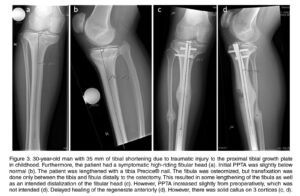

Sob a coordenação do Dr. Marcelo Pigatto D’Amado, membro da Sociedade Brasileira de Ortopedia e Traumatologia e da AO Foundation, o CBOT é pioneiro no uso de hastes intramedulares motorizadas (PRECICE, FITBONE) para alongamento ósseo no Brasil.